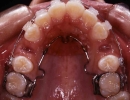

リンガルアーチ

構造

ナンスやパラータルバーと同じように、バンドを使って石膏模型上で製作します。ワイヤーを歯の裏側の形に合わせて軽く接触するように曲げてあり、これを主線と言います。このままで使うこともありますが、裏側から歯を押し出すような力を加えるときには、補助断線を付けて使うときもあります。

装置使用の目的

①歯を裏側から押し出したり、引っ張ったりするときの土台として使う場合と ②マルチブラケット装置や上顎前方牽引装置を使用するときの土台(固定源)として装着する場合と ③小児期に六歳臼歯が動かないように留めておくために使う場合によく用いられる装置です。それぞれ目的は違っても装置の基本構造は同じで、写真のように歯の裏側に少し太めの針金を沿わせ、奥歯に固定したバンドと一緒に一体化させて留めてあります。患者さんが自分で取り外すことはできませんが、調節が必要なときは先生が外して、調整後また留め直すという操作を繰り返していきます。

歯を裏側から押し出すために使う場合は、写真のように主線に補助的にスプリングを付けるときもあります。マルチブラケット装置と併用する場合は、治療期間の大体半分くらい継続して付けておきますが、治療後半には時期を見て撤去します。